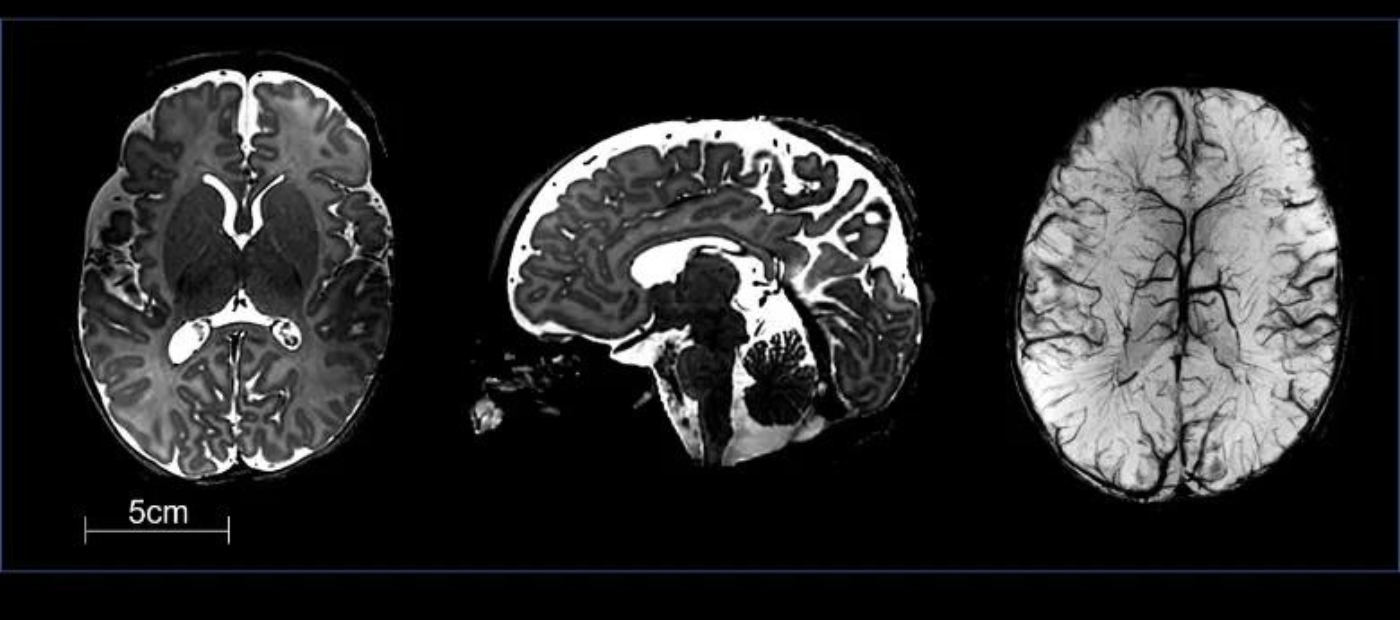

Results found that the optimised portable MRI scanner could effectively detect both normal brain anatomy, as well as a wide range of clinically important abnormalities with sufficient contrast, signal, and detail.

Portable MRI scanners (as pictured) could be used to test babies at their cot-side